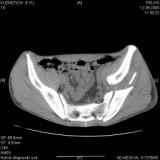

Уважаемые коллеги! Хотелось бы услышать совет по тактике лечения представлленого больного.Поступил после лечения в одном изотделений области. Травма 2,5 месяца назад. После выведенияиз шока был произведен остеосинтез перелома бедра, предплечья, до перевода к нам проводилосьвытяжение по оси шейки бедра за стержень, введенный в большой вертел. На сегодня деформацияригидна, клинически мобильности не определяется. Заранее признателен. P.S. Данный вид травм не включен в перечень "высокотехнологичных операций", направить длялечения по квотам Минздрава очень сложно.

Это обзорные и косые снимки

Привет, Леонид. Оскольчатый высокий двухколонный перелом в такие сроки трогать не надо, т.к. это про такие переломы сказано: "кто с ножом на Ж. пойдет тот в ней и останется...".